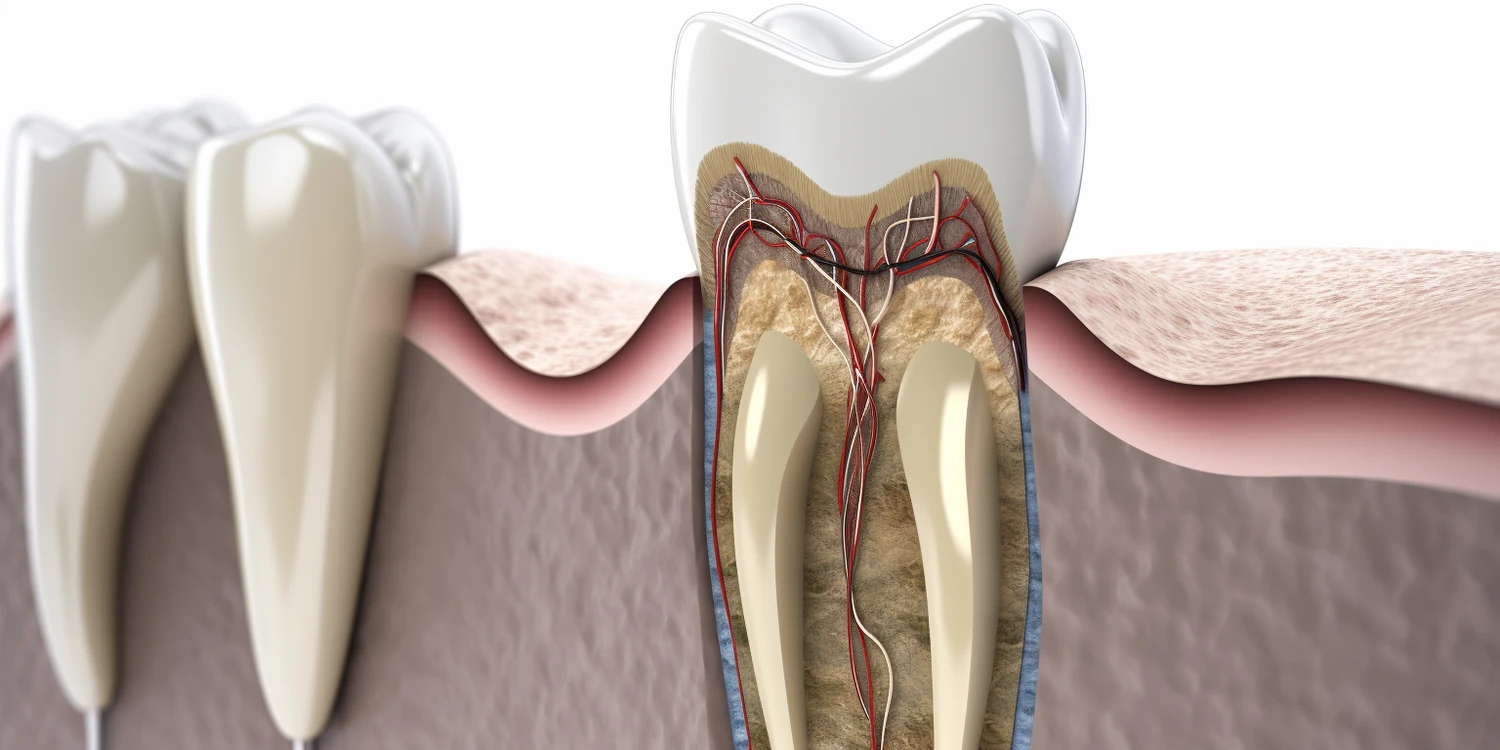

Dentysta nie zajmuje się wyłącznie zębami; jego zakres pracy obejmuje również inne aspekty zdrowia jamy ustnej oraz tkanek otaczających zęby. Stomatologia to dziedzina medycyny skupiająca się na diagnostyce i leczeniu schorzeń związanych zarówno ze zębami, jak i dziąsłami czy błoną śluzową jamy ustnej. Dentyści przeprowadzają zabiegi związane z leczeniem chorób dziąseł, takich jak zapalenie dziąseł czy paradontoza, które mogą prowadzić do utraty zębów jeśli nie zostaną odpowiednio leczone. Ponadto dentyści zajmują się także diagnostyką nowotworów jamy ustnej oraz innymi schorzeniami tkanek miękkich w obrębie jamy ustnej.